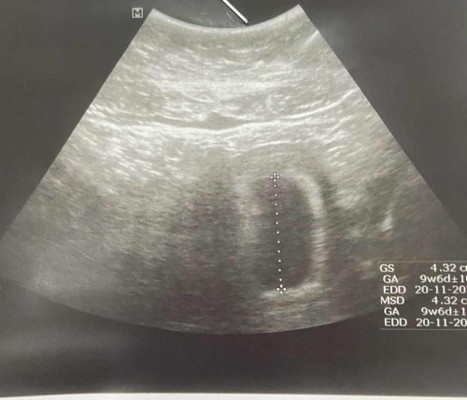

พอดีเราพึ่งตรวจเจอว่าตัวเองตั้งครรภ์เมื่อ2สัปดาห์ที่แล้วค่ะ ซึ่งโดยปกติแล้วเราเป็นคนที่ประจำเดือนมาไม่ปกติส่วนมากเดือนเว้นเดือนค่ะ เพราะเราเป็นคนน้ำหนักตัวเยอะ 100+ และวันนี้ได้ไปอัลตร้าซาวด์มาปรากฎว่าเจอแต่ถุงการตั้งครรภ์แต่ไม่เจอตัวอ่อนค่ะ เคสแบบนี้มีเยอะมั้ยคะ และเรายังมีหวังที่จะได้เห็นตัวน้องมั้ยคะเพราะอาทิตย์หน้าเค้านัดไปซาวด์ซ้ำอีกรอบนึง อดกังวลไม่ได้เลยค่ะ ท้องแรกด้วย😣😣 #ขอบคุณสำหรับคำคอมเม้นล่วงหน้าค่ะ